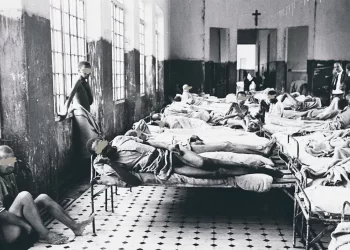

Relatório revela condições críticas em manicômios judiciários no Brasil

Um levantamento realizado pelo Conselho Federal de Psicologia (CFP) em parceria com o Conselho Nacional de Justiça (CNJ) aponta que...